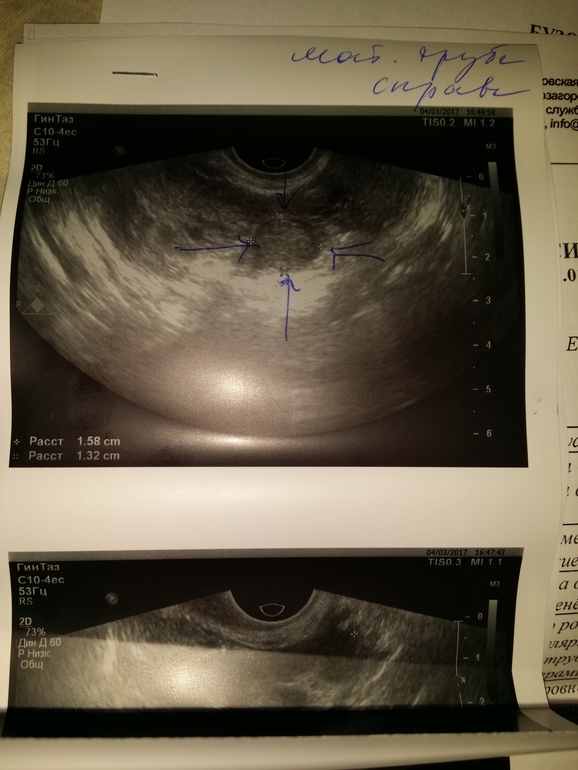

Вб,если кому фото интересно)

Замершая беременностьА вот как она п*скуди*а на узи выглядит 😡😈в не самой распространенной форме(((истмический отдел(13 % конечно же Я!!!!блин.

Меня ВЫПИСАЛИ,ну почти,я ушла сама,выписка была на вторник(так как хгч упал немного за 4 дня с 109 до 72,вердикт был рассосалась в трубе все норм)😄и я сбежала от них.не стала ждать понедельник. Узи это сегодня в платной клинике.жду понедельник иду а жк.меня уверили 3 врача что замершая,не порвет ничего.хгч не растет 2 неделю.а понедельник в другой стационар.

Очень жаль, что у вас так вышло... Недавно переписывались с вами, думали, что просто остатки...А тут. Как я понимаю,врачи бсмп не увидели пя в трубе? И решили,что это маточная зб? В принципе,если они тоже подумали,что это остатки и ХГЧ маленький, то можно отпускать, постепенно все само выйдет. Я, конечно,была за гистеру,но и их тактика имеет место быть.

У вас трубу сохранили? Срок маленький,ХГЧ изначально был небольшой, поэтому наверное обойдется...